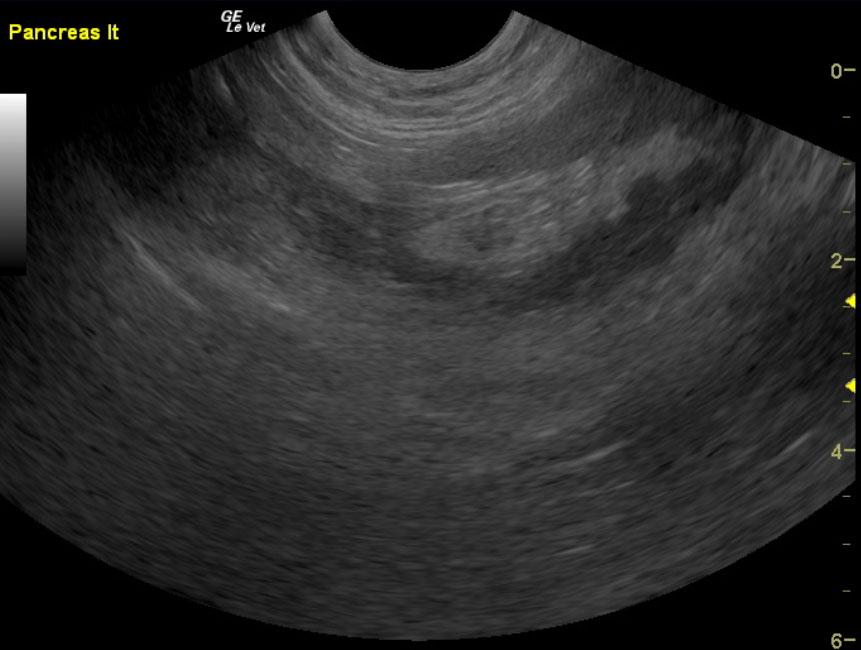

A 9-year-old MN DSH was presented for evaluation of lethargy, inappetence, and diarrhea. On physical examination, moderate dental tartar, poor body condition (BCS 2/5) and a dull unkempt hair coat was evident. On urinalysis moderate leukosuria, mild hematuria, and normal SG with moderate leukocytes, 2+ protein, 6.5 pH, urine specific gravity 1.035 with a small amount of blood. Abnormalities on CBC and serum biochemistry were neutrophilia with toxic changes, hyperglycemia, hyperglobulinemia, elevated fPL, and low folate and low B12. Negative FeLV, negative FIV, and negative heartworm assay. On survey radiographs mild hepatomegaly was evident.